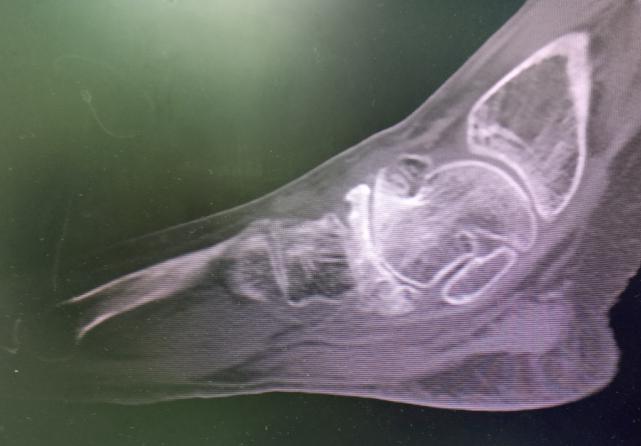

立即进行了CT检查,结果发现患者左足舟骨发生了坏死。(图1图2)诊断为:左足舟骨骨坏死合并距舟关节骨关节炎。

图1

图2